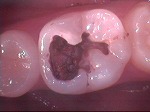

◆ドックベストセメント療法

削らないむし歯治療で注目されているセメントです。

セメントの殺菌効果により、通常のでは神経を抜くであろう深いむし歯治療においても有効です。

ドックスベストセメントを使用することで歯の神経保存率が高まります。

この治療は自費治療となります。

ドックスベストセメント

~初診~

~歯髄に近い深い虫歯~

~ドックベストセメント処置~

~グラスアイオノマー仮封~

~CR充填~